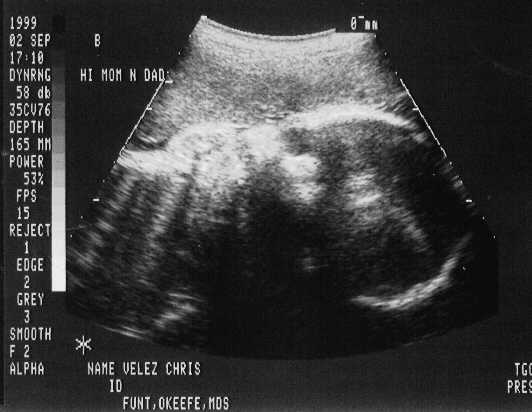

September 02, 1999 Sonograms

Kris is in her 33rd week. She can go in labor in 3 weeks!

Patrick weighs 4.6 pounds.

The doctor says he can't believe how close they are in weight. They are almost NEVER this close in size.

Patrick Joseph

sono-0902-b1.JPG - 22.9 K